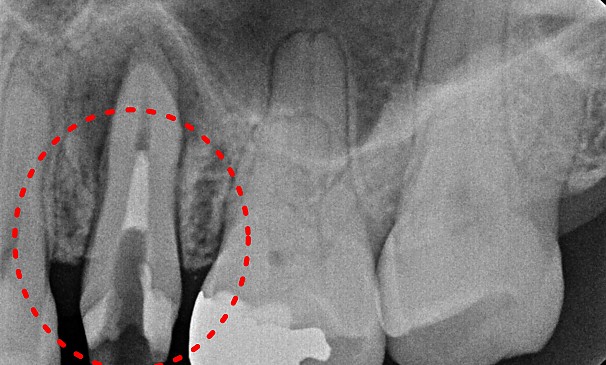

특수재신경치료

최OO님 전후사진 | 치료 기간 : 1주

치료 전

치료 후